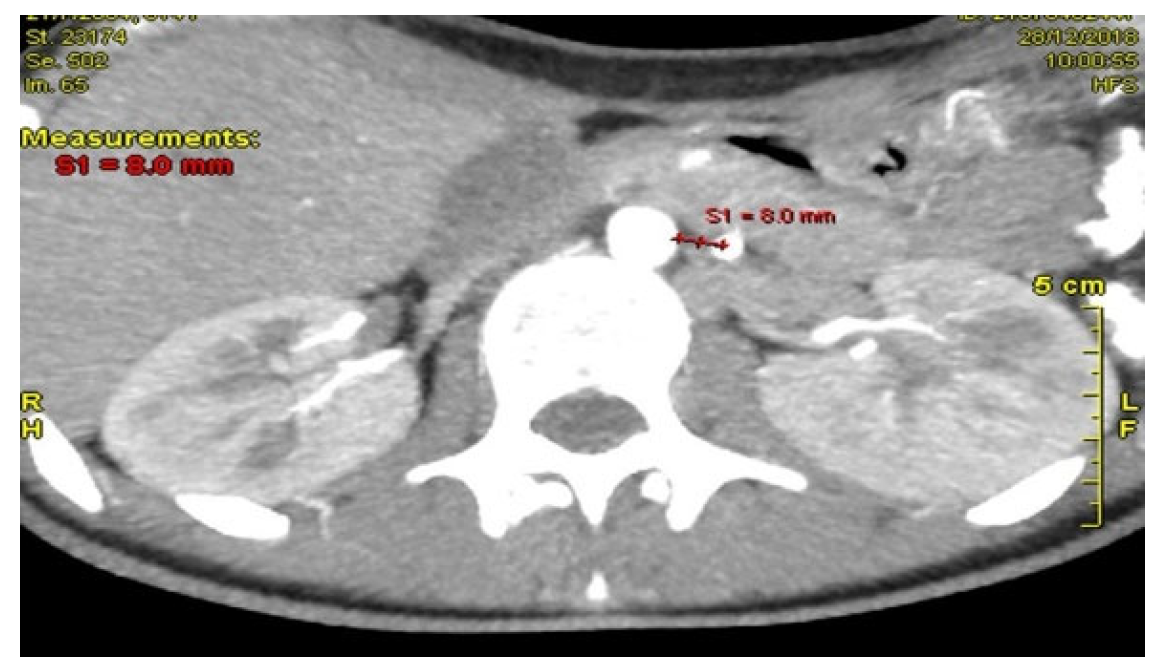

Computed Tomography Angiography (CTA) Figure 2, provided definitive anatomical correlation. At the level where the third portion of the duodenum crosses between the abdominal aorta and the SMA, the aortomesenteric angle was significantly reduced to 6° (normal: 38–56°), Figure 3 and the aortomesenteric distance measured 4 mm (normal: >10 mm, with <8 mm considered pathological). Figure 4 These findings were consistent with SMAS, a rare condition caused by vascular compression of the third portion of the duodenum between the SMA and the aorta.

Figure 3. CTA: The aortomesenteric distance measured 4 mm.

Figure 4. CTA: Findings consistent with superior mesenteric artery SMAS.